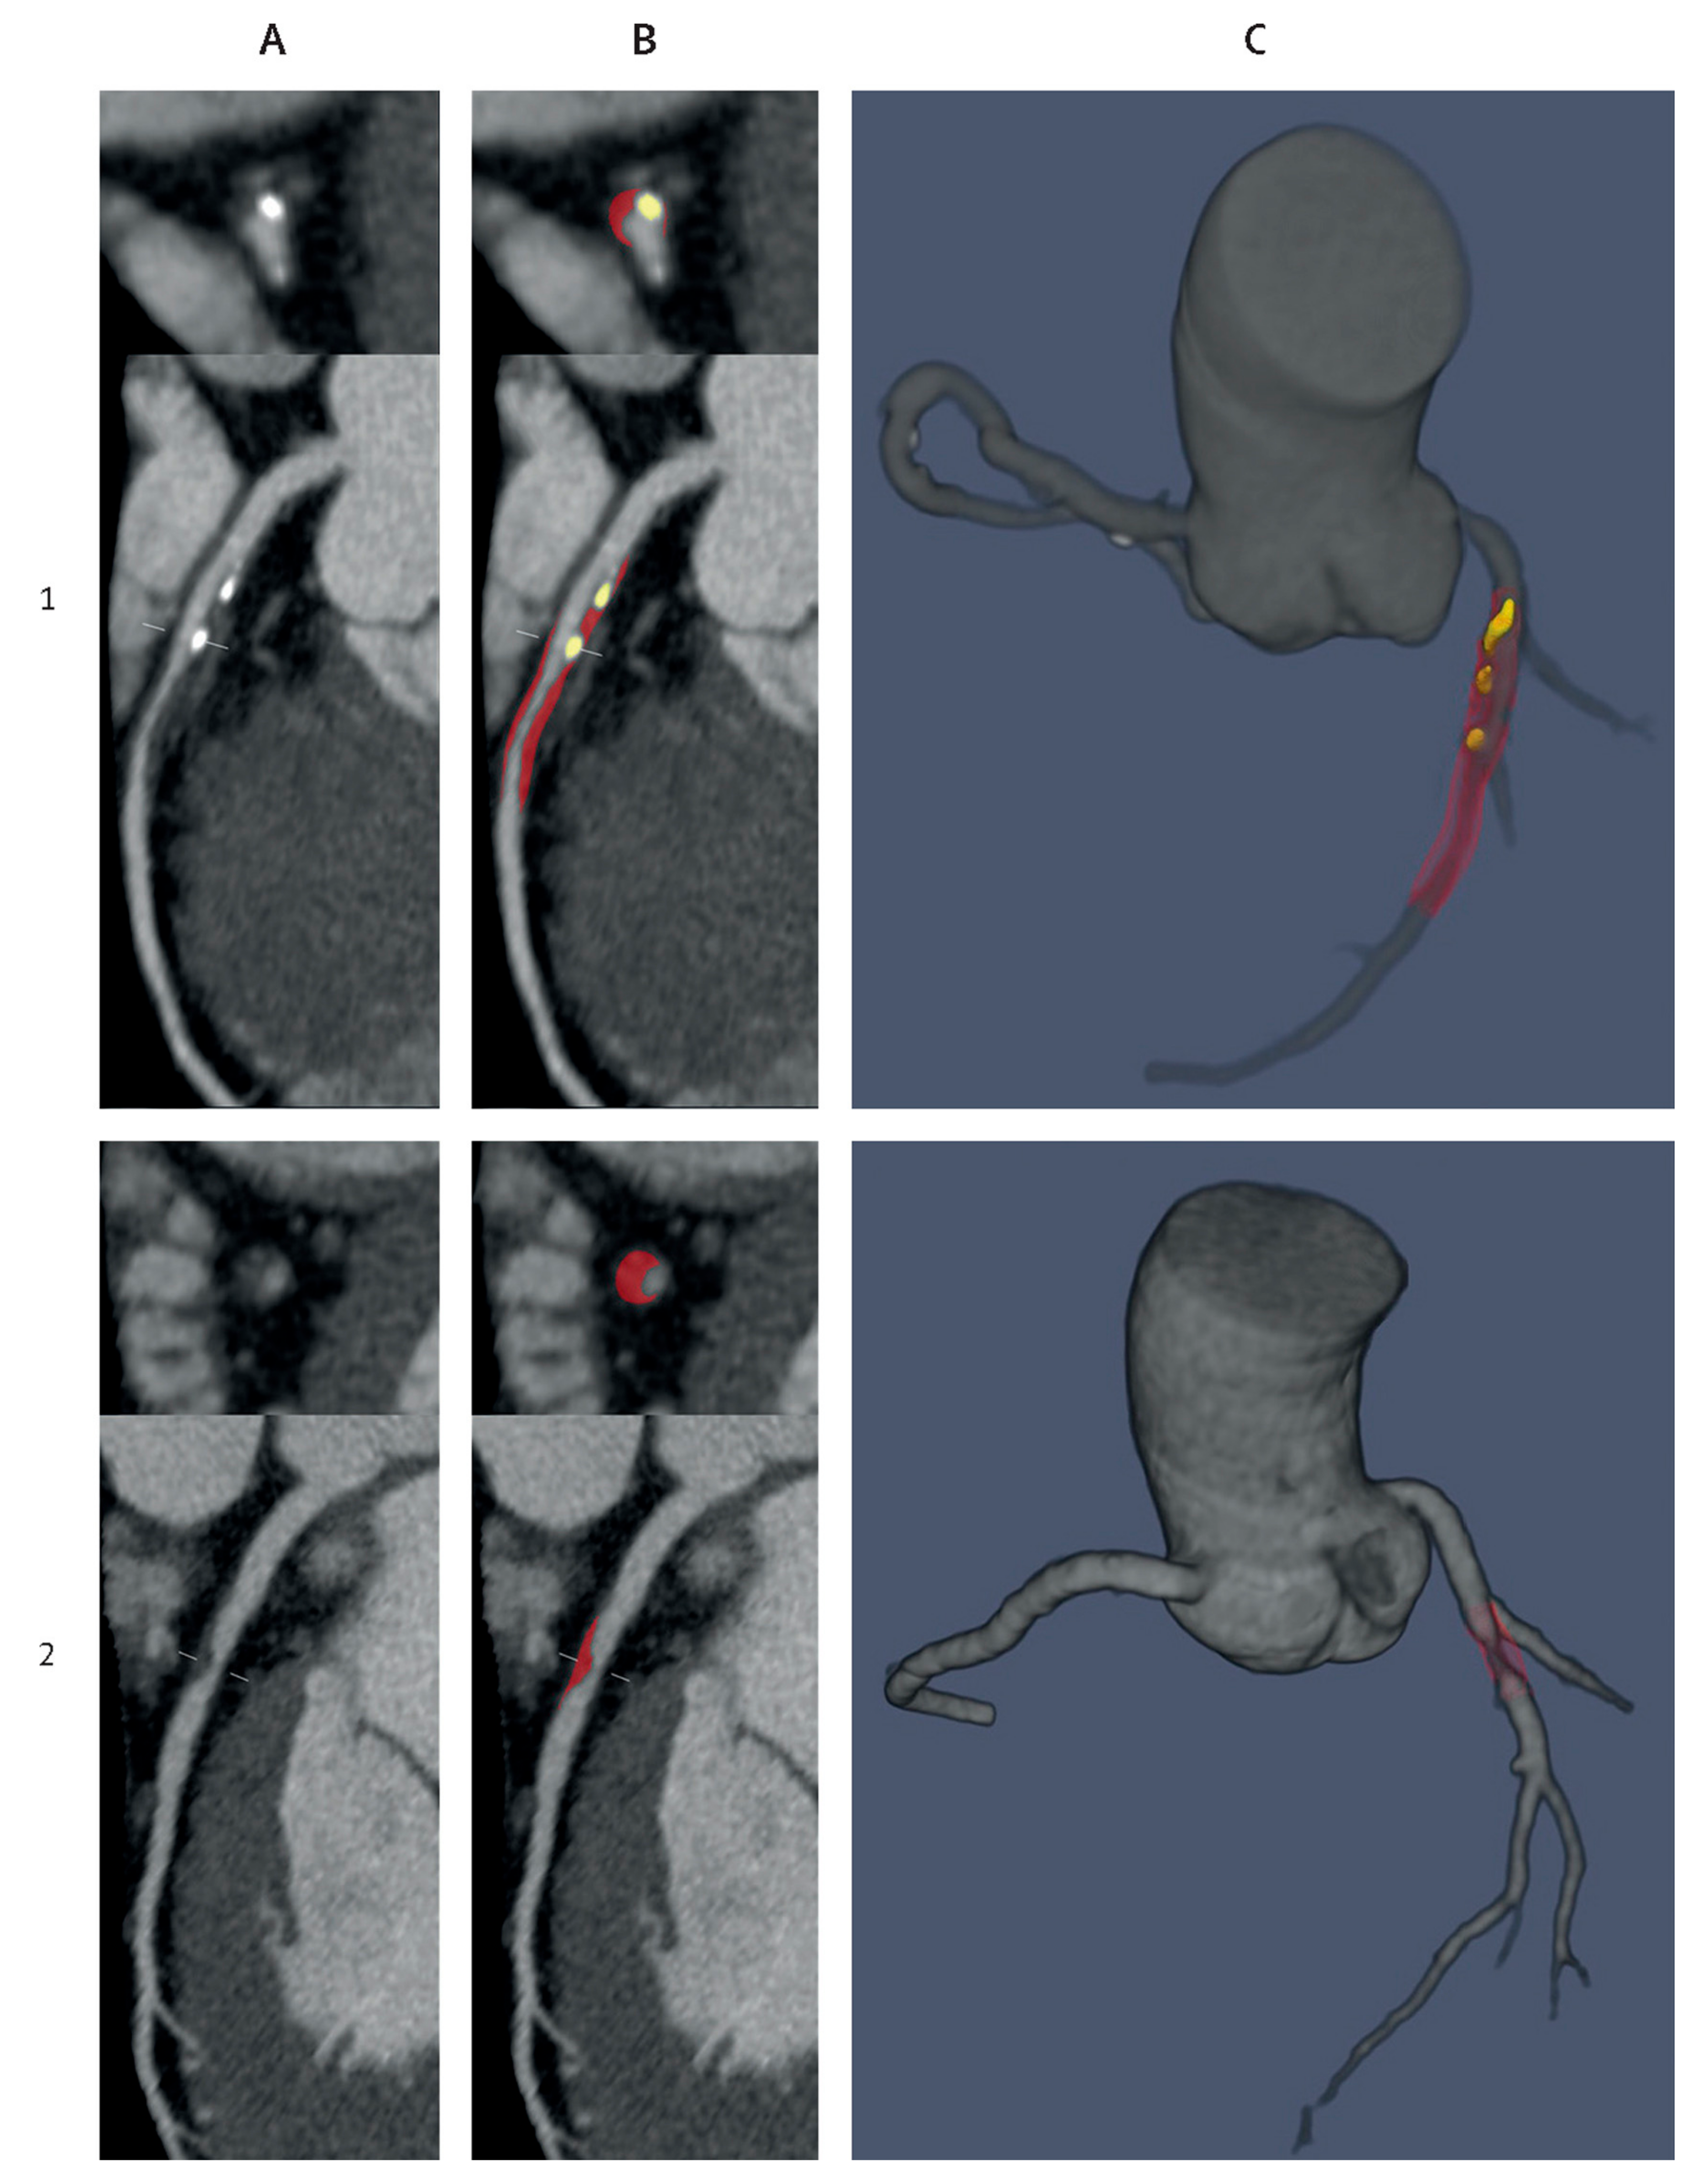

- Lareyre, F.; Adam, C.; Carrier, M.; Dommerc, C.; Mialhe, C.; Raffort, J. A fully automated pipeline for mining abdominal aortic aneurysm using image segmentation. Sci. Rep. 2019, 9, 13750. [Google Scholar] [CrossRef] [PubMed]

- Spinella, G.; Fantazzini, A.; Finotello, A.; Vincenzi, E.; Boschetti, G.A.; Brutti, F.; Magliocco, M.; Pane, B.; Basso, C.; Conti, M. Artificial Intelligence Application to Screen Abdominal Aortic Aneurysm Using Computed tomography Angiography. J. Digit. Imaging 2023, 36, 2125–2137. [Google Scholar] [CrossRef] [PubMed]